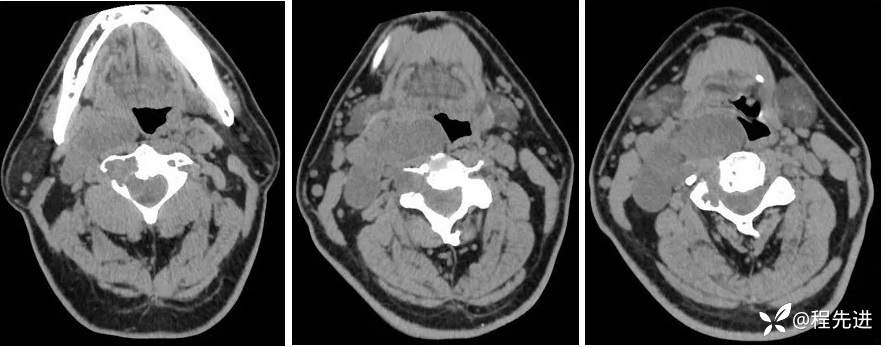

平扫: